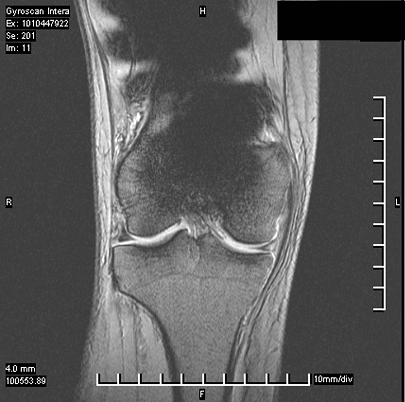

⚠️ ¿Qué son los artefactos en la resonancia asociados a prótesis?

Aunque una prótesis sea compatible, eso no garantiza que no distorsione la imagen.

Los artefactos son un efecto físico del metal sobre el campo magnético.

Como explico a mis pacientes, “aunque una prótesis sea compatible con resonancia magnética, no implica que no cree artefactos en la imagen”.

Un caso típico es el de los brackets o prótesis metálicas cercanas a la zona a estudiar: la resonancia es segura, pero puede no servir para diagnosticar correctamente.